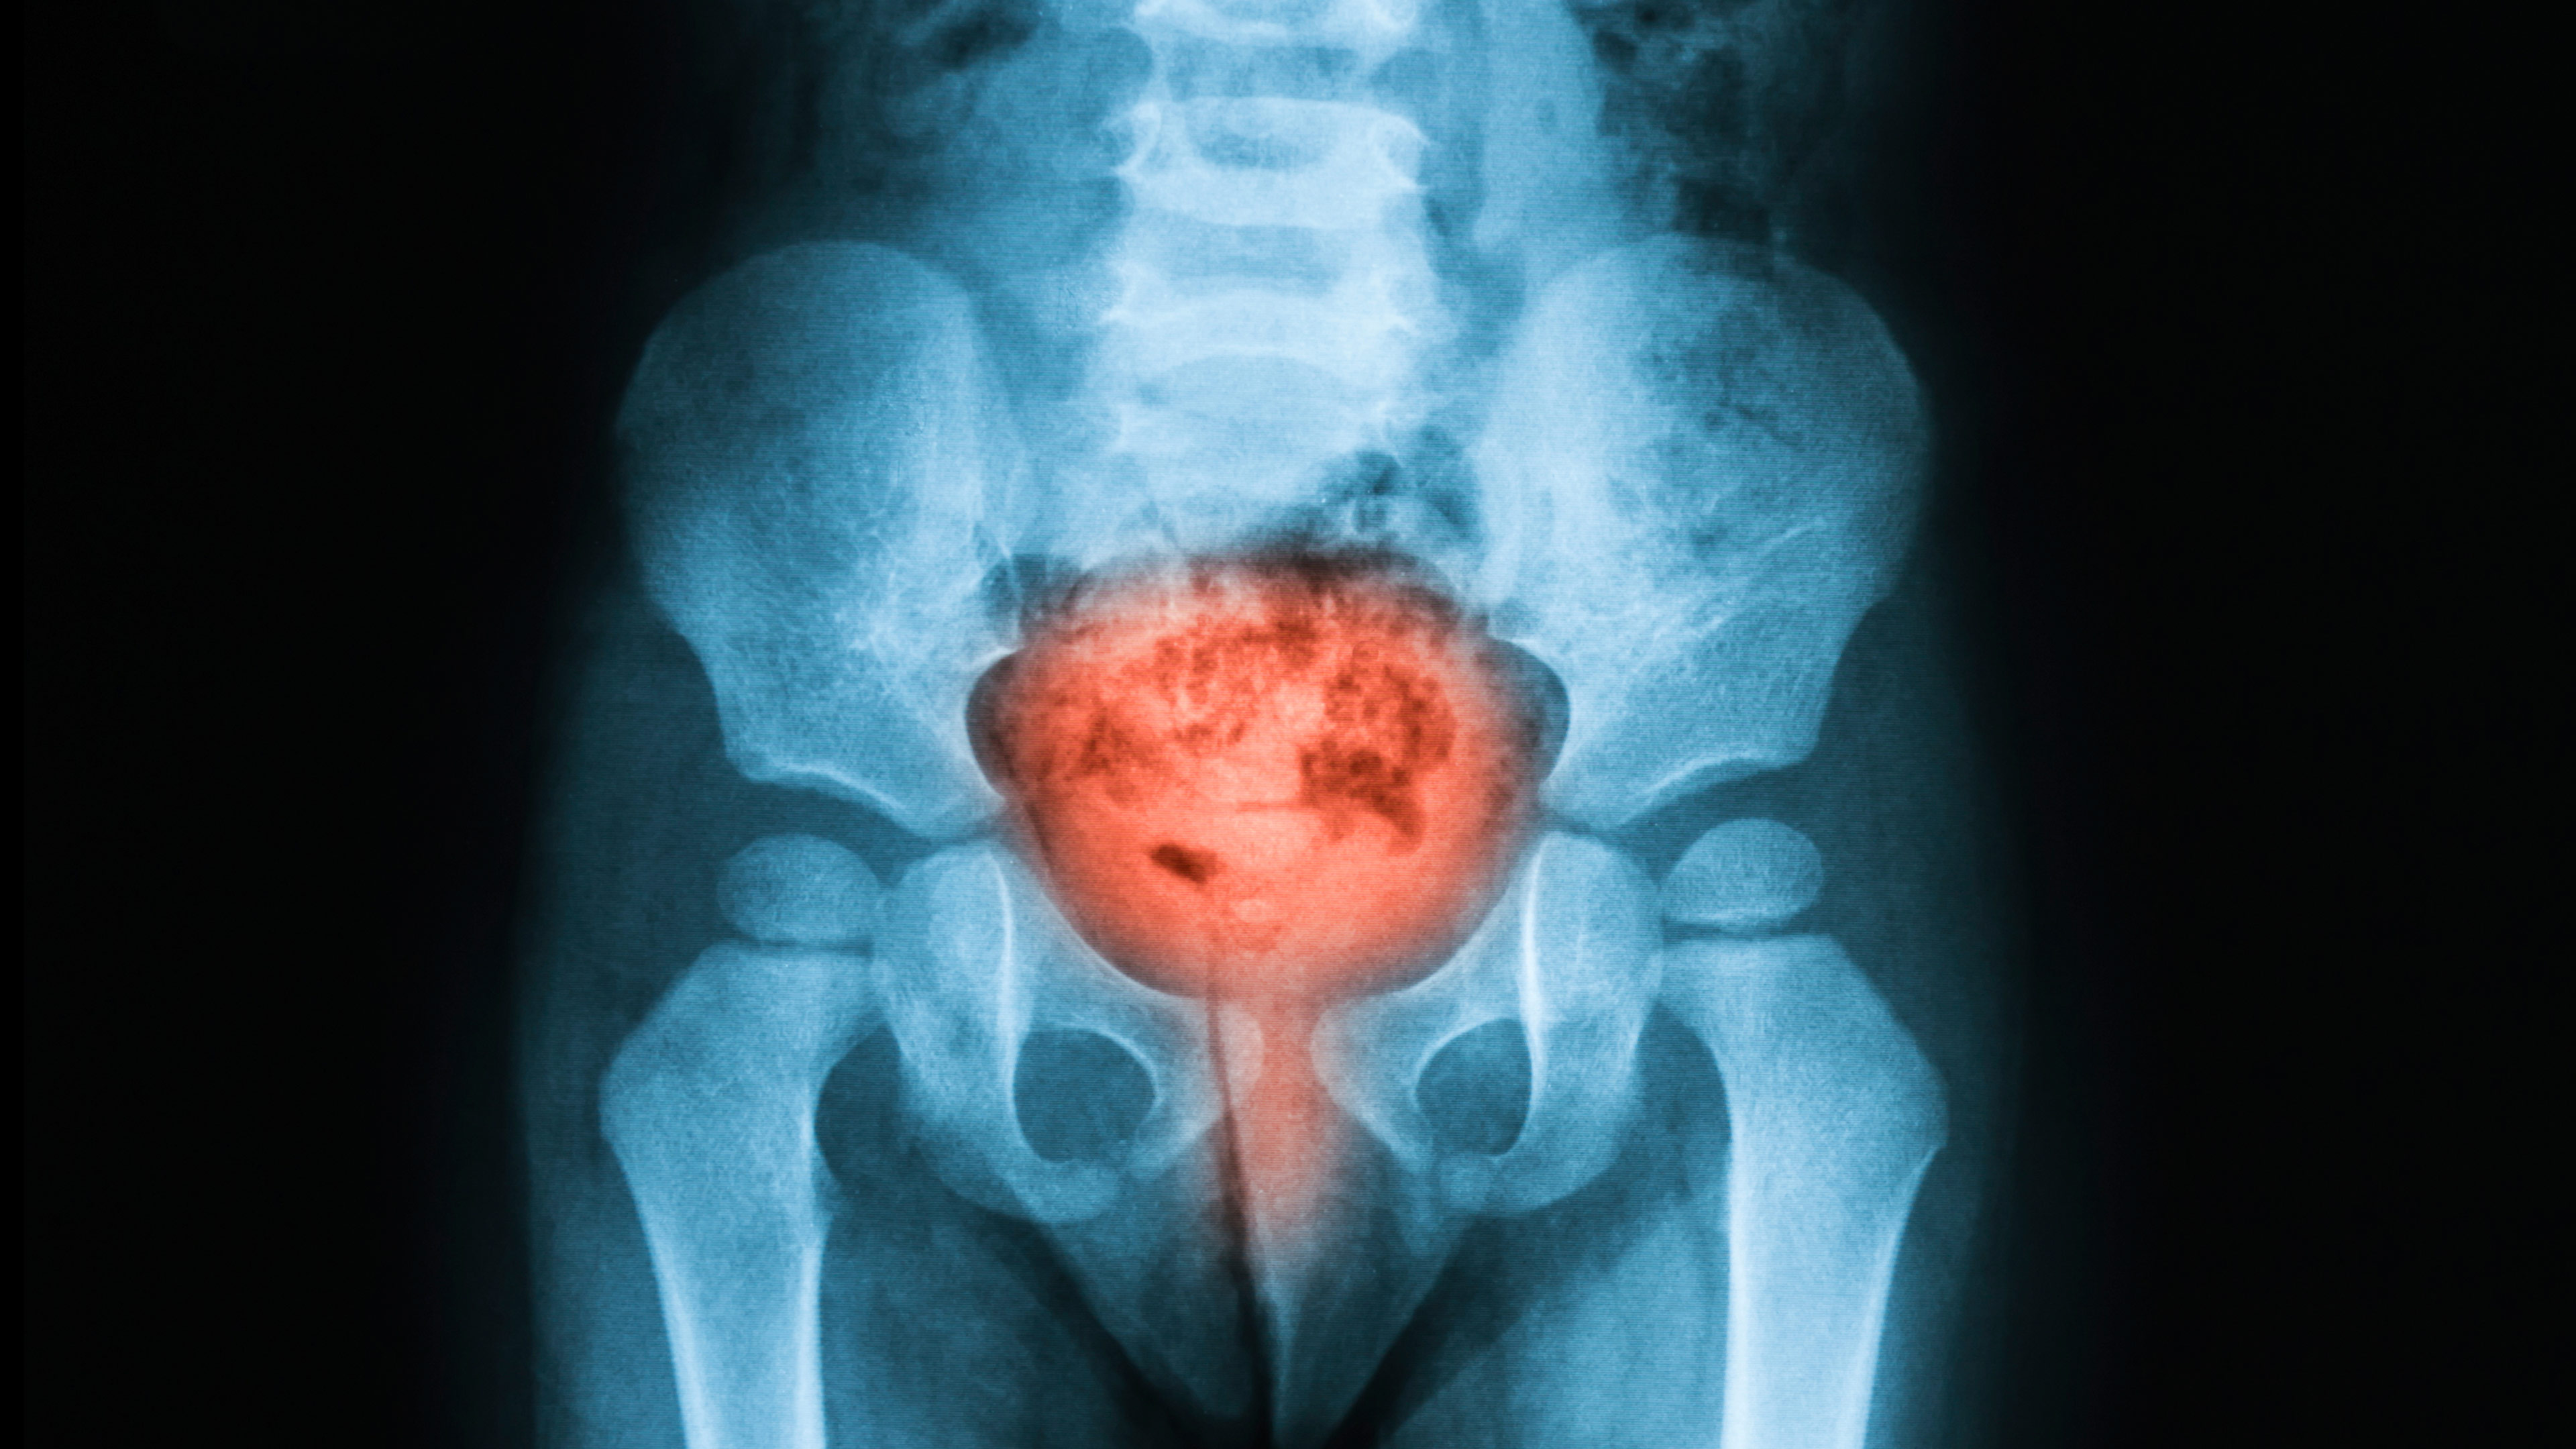

The use of certification worksheets provide both the pilots’ treating physicians and the AME with the information needed for office certification. The Bladder Cancer Worksheet details the needed information for a CACI issuance. Take the worksheet and the medical reports to your AME who will confirm that everything on the worksheet meets the guidelines and can issue your certificate at the time of the FAA physical examination.